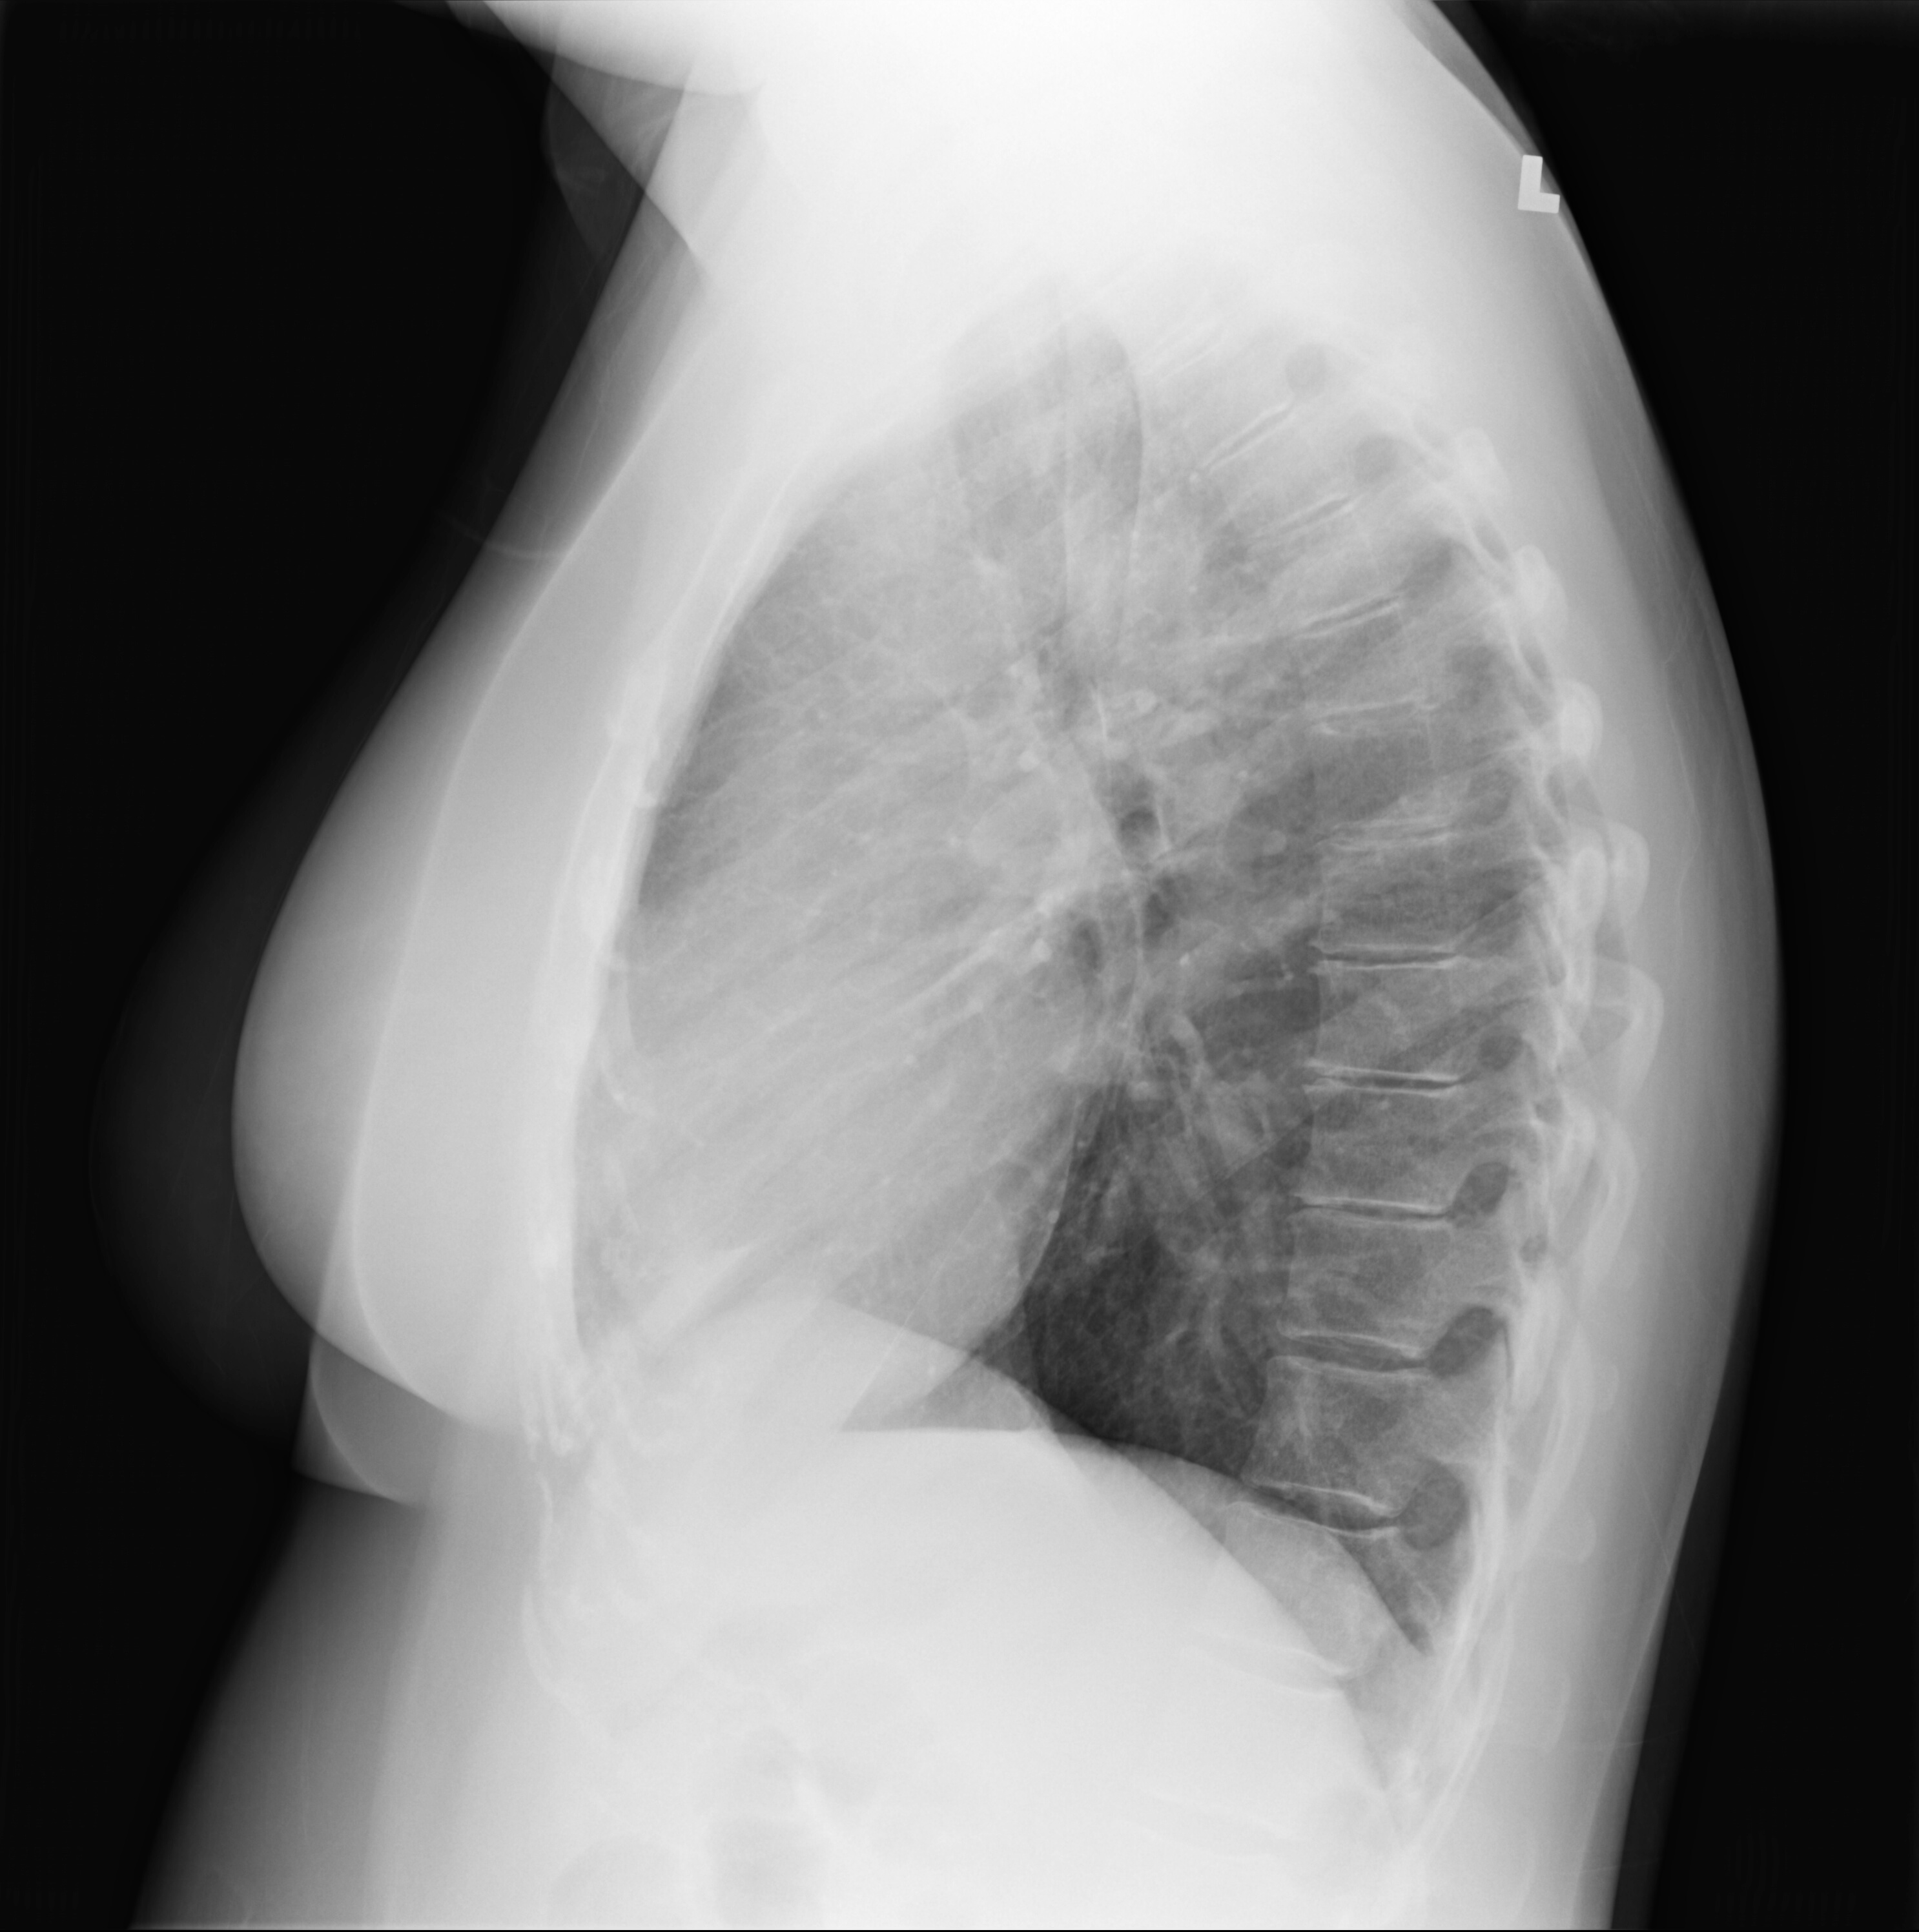

The work comprises images and video I shot while my dad was alive, during the funeral, and when clearing out his flat. I’m also incorporating his diaries and documents, and photographing items that he left behind, as well as manipulating family snapshots and medical imaging of him and myself. Threads running through the project include suppressed mad histories and the burgeoning Consumer/ Survivor / X-inmate movement, astrophysics (an interest we shared), ecology (his passion and obsession), and how death and grieving are erased in Western culture. The project will be presented as an exhibition of photographs and video, as well as eventually a book.